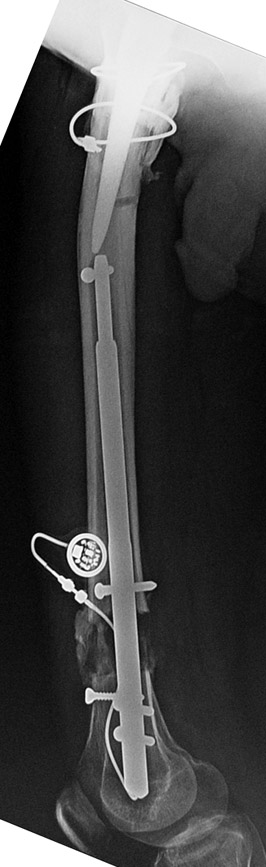

İM Motorlu Çivi ile Uzatma

FITBONE – Bilgisayar Kontrollü Intramedullar Uzatma Çivisi

Tamamen vücut içerisinde kalan bir donanıma sahip, dereceli olarak iki kemik arasında uzatma yapabilmektedir. Üstün teknik altyapısı sayesinde, çivi telemetrik olarak kumanda edilmekte ve hiçbir dış bağlantıya ihtiyaç duymamaktadır.